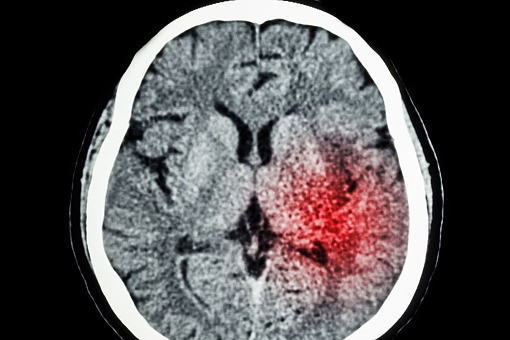

Według Światowej Organizacji Zdrowia udar mózgu to nagłe, zagrażające życiu zaburzenie czynności mózgu trwające dłużej niż 24 godziny (o ile wcześniej nie dojdzie do zgonu), spowodowane przyczynami naczyniowymi. O skuteczności leczenia decyduje przede wszystkim czas. Im szybciej zostanie udzielona pomoc, tym większe są szanse na powrót do zdrowia.

W Polsce w latach 2018–2022 z powodu udaru mózgu rocznie hospitalizowano średnio 80 tys. pacjentów, z czego zdecydowana większość przypadków (ok. 87 proc.) dotyczyła udarów niedokrwiennych. Jak pokazują dane NFZ, łączne koszty leczenia pacjentów hospitalizowanych z powodu udaru mózgu w latach 2018–2022 przekroczyły 4 mld zł. Według amerykańskich danych udar mózgu jest drugą najczęstszą przyczyną zgonu lub niepełnosprawności.